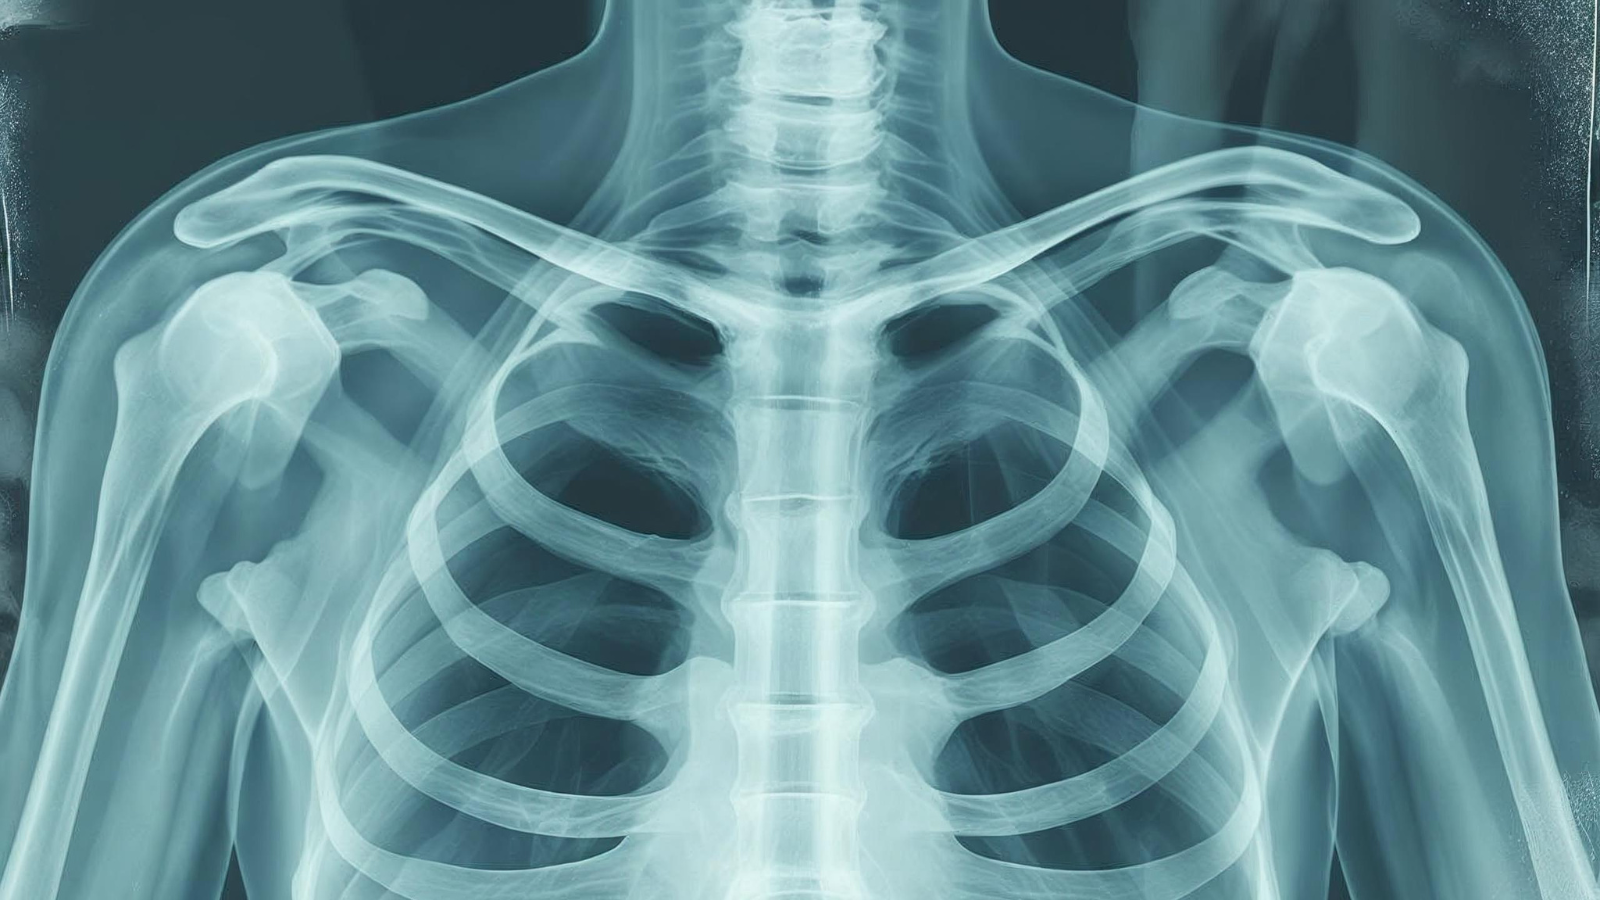

Việc chụp X-quang sẽ giúp bác sĩ đánh giá chính xác tình trạng xương và trả lời cụ thể cho bạn gãy xương sườn bao lâu thì lành đối với trường hợp cá nhân của mình.